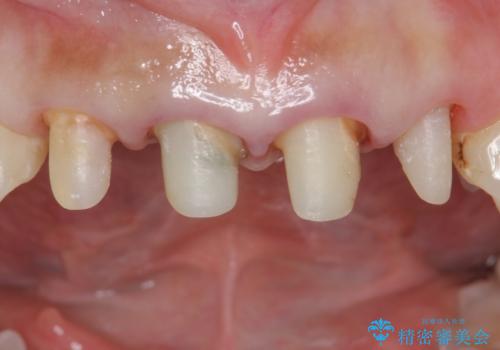

色調・適合ともに改善するために一度被せ物を外し、歯の形を整えた後に新しい被せ物を装着していきます。

歯ぐきの炎症を抑えつつ、被せ物と歯との境目がわからなくなるよう被せ物を装着しました。